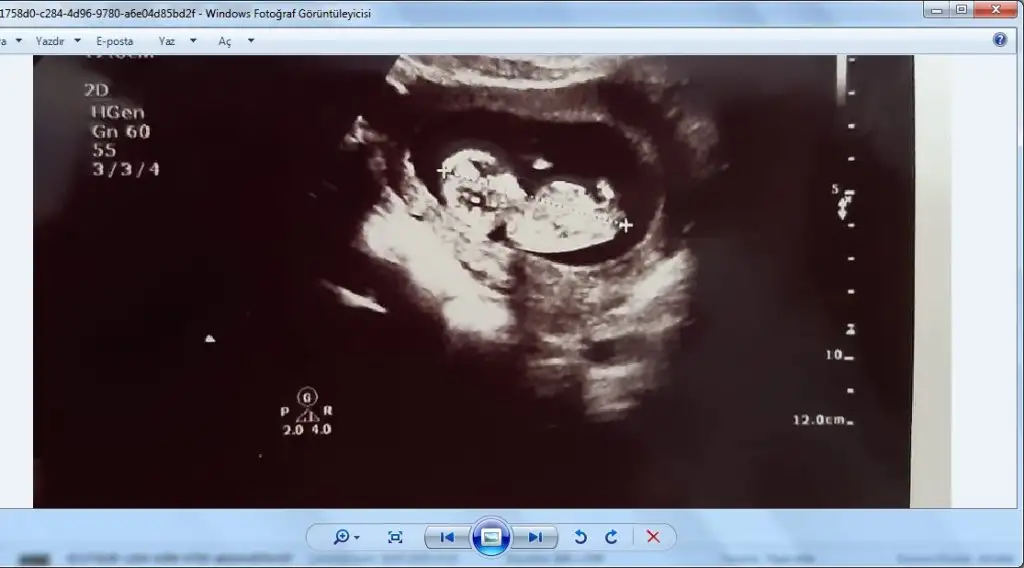

Kızlar tahminleri alalım nub prosu var dediler geldik.

Kafam karisti bunlarda da erkek gibi pipi gorunuyor sanki